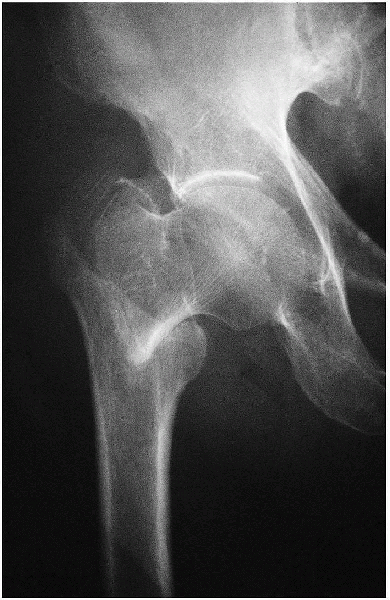

Anteroposterior view of the pelvis (Fig. 23-4)

Anteroposterior and cross-table lateral view of the involved proximal femur (Figs. 23-5 and 23-6).

FIGURE 23-4. Standard radiographic view: anteroposterior view of the pelvis, showing a left intertrochantene hip fracture.

FIGURE 23-5. Standard radiographic view: anteroposterior view of the involved proximal femur.